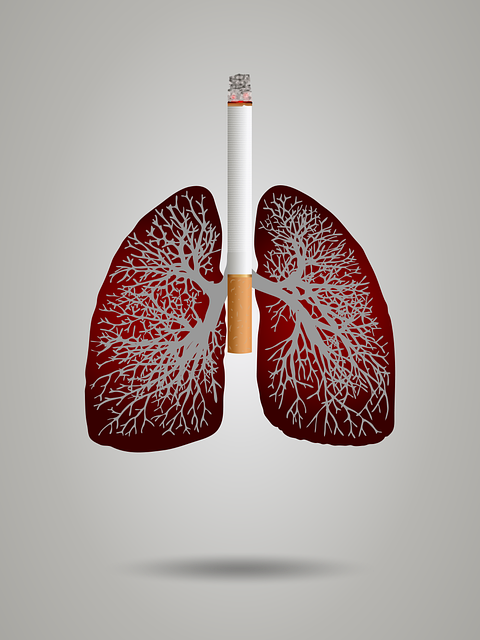

폐암의 주요 원인으로 지목되는 것은 흡연으로 알려져 있으며 흡연자의 경우 비흡연자에 비해 폐암에 걸릴 가능성이 20 이상 높다고 알려져 있습니다. 요즘에는 대기오염으로 인해서 호흡기 질환에 걸리는 사람들도 점차 많아지다 보니 폐암에 의한 사망자가 늘어가는 추세입니다.

폐암을 예방하기 위한 가장 좋은 방법은 금연하는 것입니다. 간접흡연 또한 주위 사람에게 피해를 주고 폐암 발병률을 높이기 때문에 사랑하는 사람들을 위해서라도 금연은 필수입니다. 대기오염이 점차 심해지면서 미세먼지가 많아져 호흡기 질환을 많이 유발합니다 그렇기 때문에 야외에 나갈 때에는 마스크 착용을 생활화하고 발암물질이 많은 곳은 피하는 것이 좋습니다.